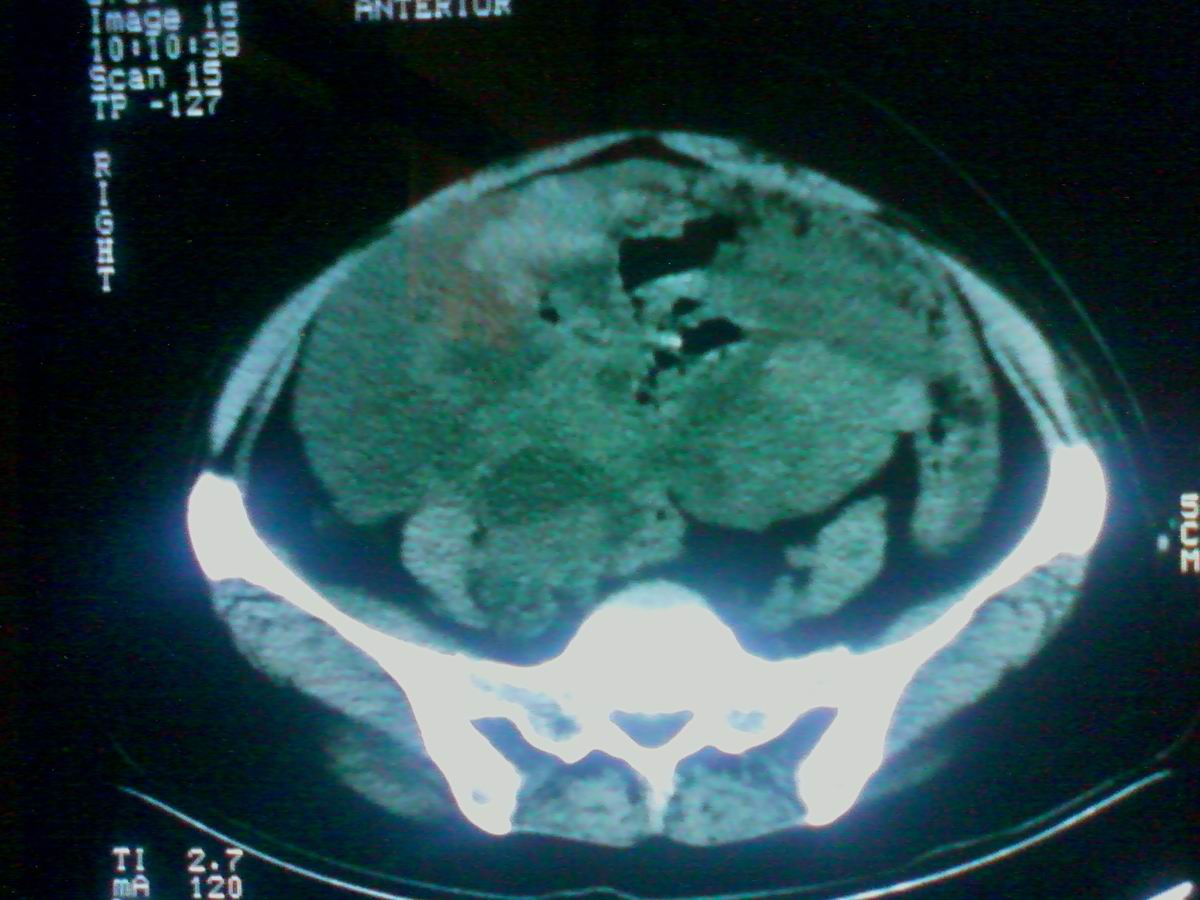

标题: CT25799:女性患者,45岁,腹胀,上腹部疼痛来诊,B超示盆腔 [打印本页]

标题: CT25799:女性患者,45岁,腹胀,上腹部疼痛来诊,B超示盆腔

考虑卵巢癌伴腹水

1)考虑卵巢恶性肿瘤。2)腹水。